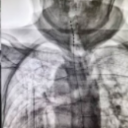

C臂透视示术中电刺激已成功置入。

手术在局麻下进行,老人全程清醒。术中,当电极启动测试时,陈奶奶激动地反馈:“麻到了!颈椎和肩胛都不痛了!”这种即时反馈确保了电极能够百分百覆盖痛区。术后一周,两位老人的疼痛视觉模拟评分(VAS,0分为无痛,10分为剧痛)从术前的8-9分骤降至2-3分,睡眠质量和情绪状态得到了质的改善。